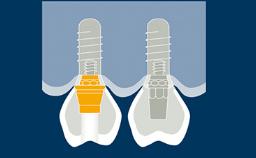

An implant abutment is the part or component that serves as support and/or retention for a dental prosthesis. The selection of the implant abutment for each individual patient case is therefore an important part of the implant-prosthodontic treatment phase. In this module, we will discuss the function of implant abutments, different implant abutment types, different abutment materials and how to select an abutment based on a prosthodontically driven process.

- identify different types of implant abutments

- list different implant abutment materials and their indications